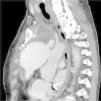

O ecocardiograma transtorácico (Figura 1) excluiu disfunção do anel mitral ou insuficiência mitral residual, com boa função sistólica global e imagem hiperecogénica (interpretada como trombo) no teto da aurícula direita, com 3,3x2cm.